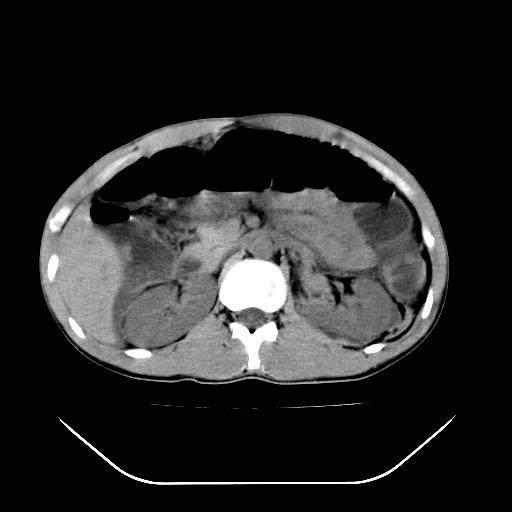

顺便请各位老师认真看看7号片

各位老师觉得胆囊是不是有点积血。我在原始片看胆囊密度不均,似有小液平面

再有就是支持楼主,胆囊7日片比5日片不仅增大许多,靠后下更见液液分层,应该是有积血。

结果收到,谢谢楼主,另外反过来看这个地方是不是游离气体影

看了各位老师的精彩点评,学到了很多东西,另外还有一点疑问,不知对否?

左胸部前肋有没有骨折?

胃大弯侧是否在5号就已经有游离气体了?